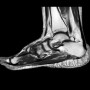

تستخدم هذه التقنية بشكل خاص في تشخيص الإصابات التي تؤثر على الأنسجة الرخوة مثل العضلات، الأربطة، الأوتار، والغضاريف، بالإضافة إلى الأنسجة العظمية. إن قدرة الرنين المغناطيسي على إظهار التفاصيل التشريحية بدقة عالية تجعله الأداة الذهبية لتشخيص الإصابات الرياضية، الحوادث، أو الحالات التنكسية.

تُعد هذه التقنية الأداة المثلى لتشخيص إصابات الأنسجة الرخوة. على سبيل المثال، في إصابات الركبة، يمكن للرنين المغناطيسي أن يكشف عن تمزق في الرباط الصليبي الأمامي (ACL) أو الغضروف الهلالي بدقة فائقة. وفي إصابات الكتف، يمكنه تحديد تمزق في الأربطة أو الأوتار مثل تمزق الكفة المدورة. هذا التشخيص الدقيق ضروري لتحديد ما إذا كانت الإصابة تتطلب علاجًا طبيعيًا أو تدخلًا جراحيًا.